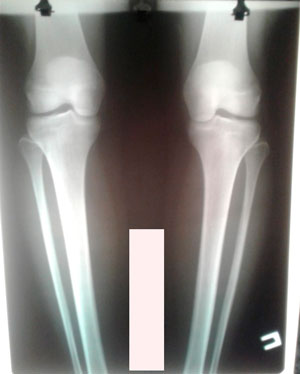

Рентген перед снятием аппаратов.

Любимая рубрика: В сравнении!

Дата операции - 17.06.2019г.

Дата снятия аппаратов -30.08.2019.

Срок сращения -73 дня.